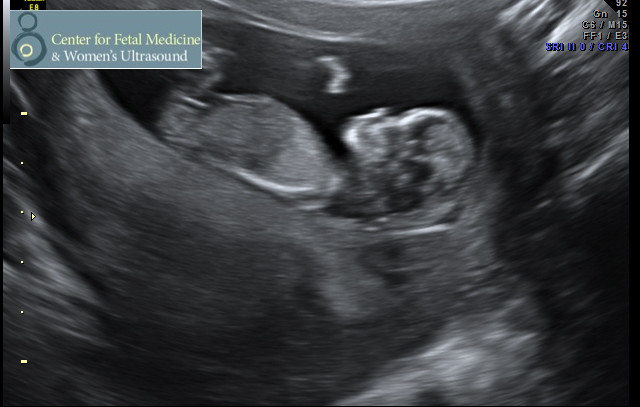

Here is my sweet little boy (we got our all clear Panorama results back today) at 12 weeks 4 days (yep, the due date moved up)! Heartbeat was 167 and he was a happy, wiggly worm. I've been bumped into March, so I wanted to wish you all the best.